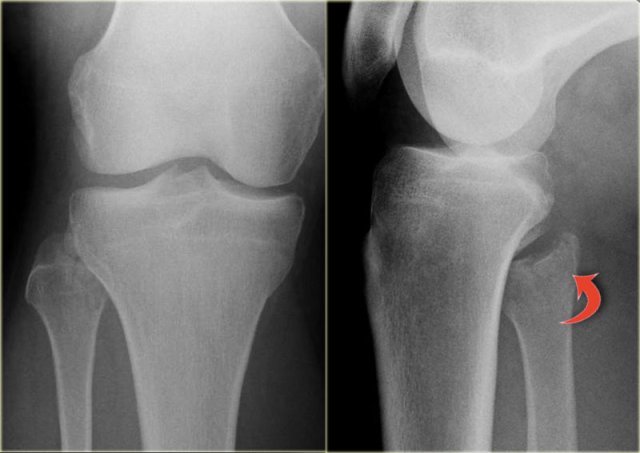

Triplane fracture Triplane fracture

At first this looks like a Weber B fracture with an oblique fracture in the fibula as seen on the lateral view (black arrows).

Notice however that this fracture line stops at the level of the epiphyseal plate.

So this is the fracture of the metaphysis in the coronal plane.

On the AP-view there is a lucency within the epiphysis, which is the epiphyseal fracture in the sagittal plane.

Notice also that the medial epiphysis is already closed, while the lateral portion is still open(blue arrows).

We have to assume that there is an epiphysiolysis of this lateral portion.

Here another example.

There is only a small metaphyseal fragment, which is usually the case (red arrow).

The fracture through the epiphysis is indicated by the blue arrow.